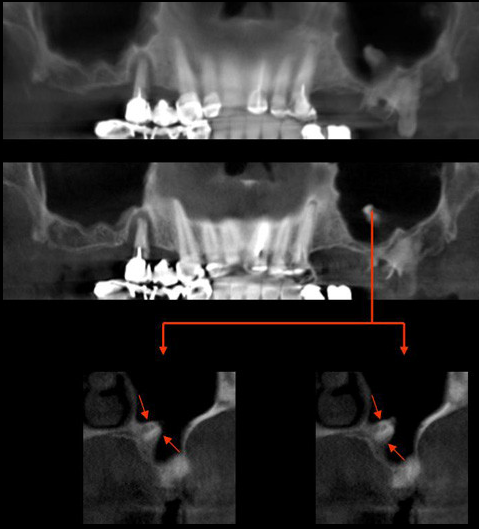

Paciente masculino 57años de edad, acude a la consulta para evaluación tomográfica previa a la colocación de implantes. En la radiografía panorámica observamos una imagen radiopaca proyectada en el antro del seno maxilar izquierdo. Se realiza estudio con tomografía volumétrica (Picasso E-WOO), se grafican cortes panorámicos, axiales, coronales y transaxiales que muestran claramente la imagen de densidad cálcica en el interior del seno maxilar izquierdo compatible con Antrolito.